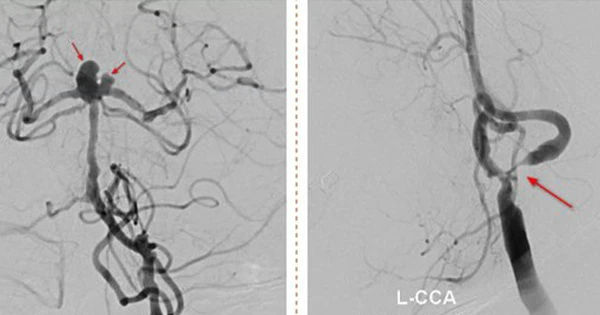

Đột quỵ đặc biệt nguy hiểm: Cuộc chiến với nhồi máu não và nguy cơ vỡ túi phình

Khám phá cuộc chiến đầy cam go của người phụ nữ đối diện với 2 loại đột quỵ đặc biệt nguy hiểm: nhồi máu não và nguy cơ vỡ túi phình. Hãy cùng tìm hiểu về quá trình can thiệp và hồi phục của bệnh nhân...